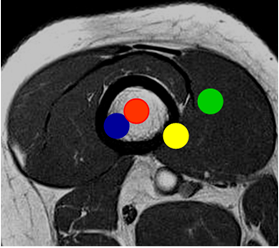

Fig 20. Localización transversal.

RM axial en T1. Zona roja: Lesión central. Azul: Excéntrica. Amarilla: Superficial y

Verde: De tejidos blandos.